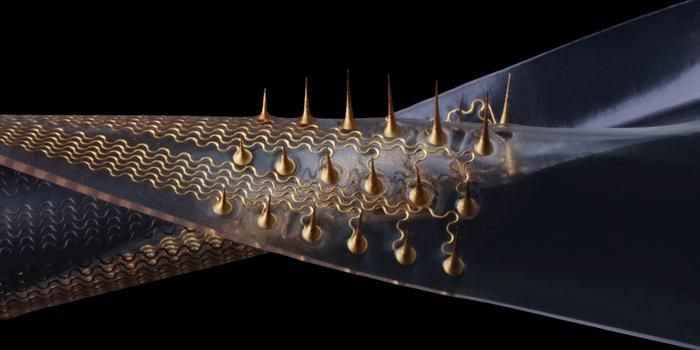

JUN 08, 2024TechnologyA team of researchers with Brigham and Women’s Hospital have designed a novel microneedle patch that is designed t ...